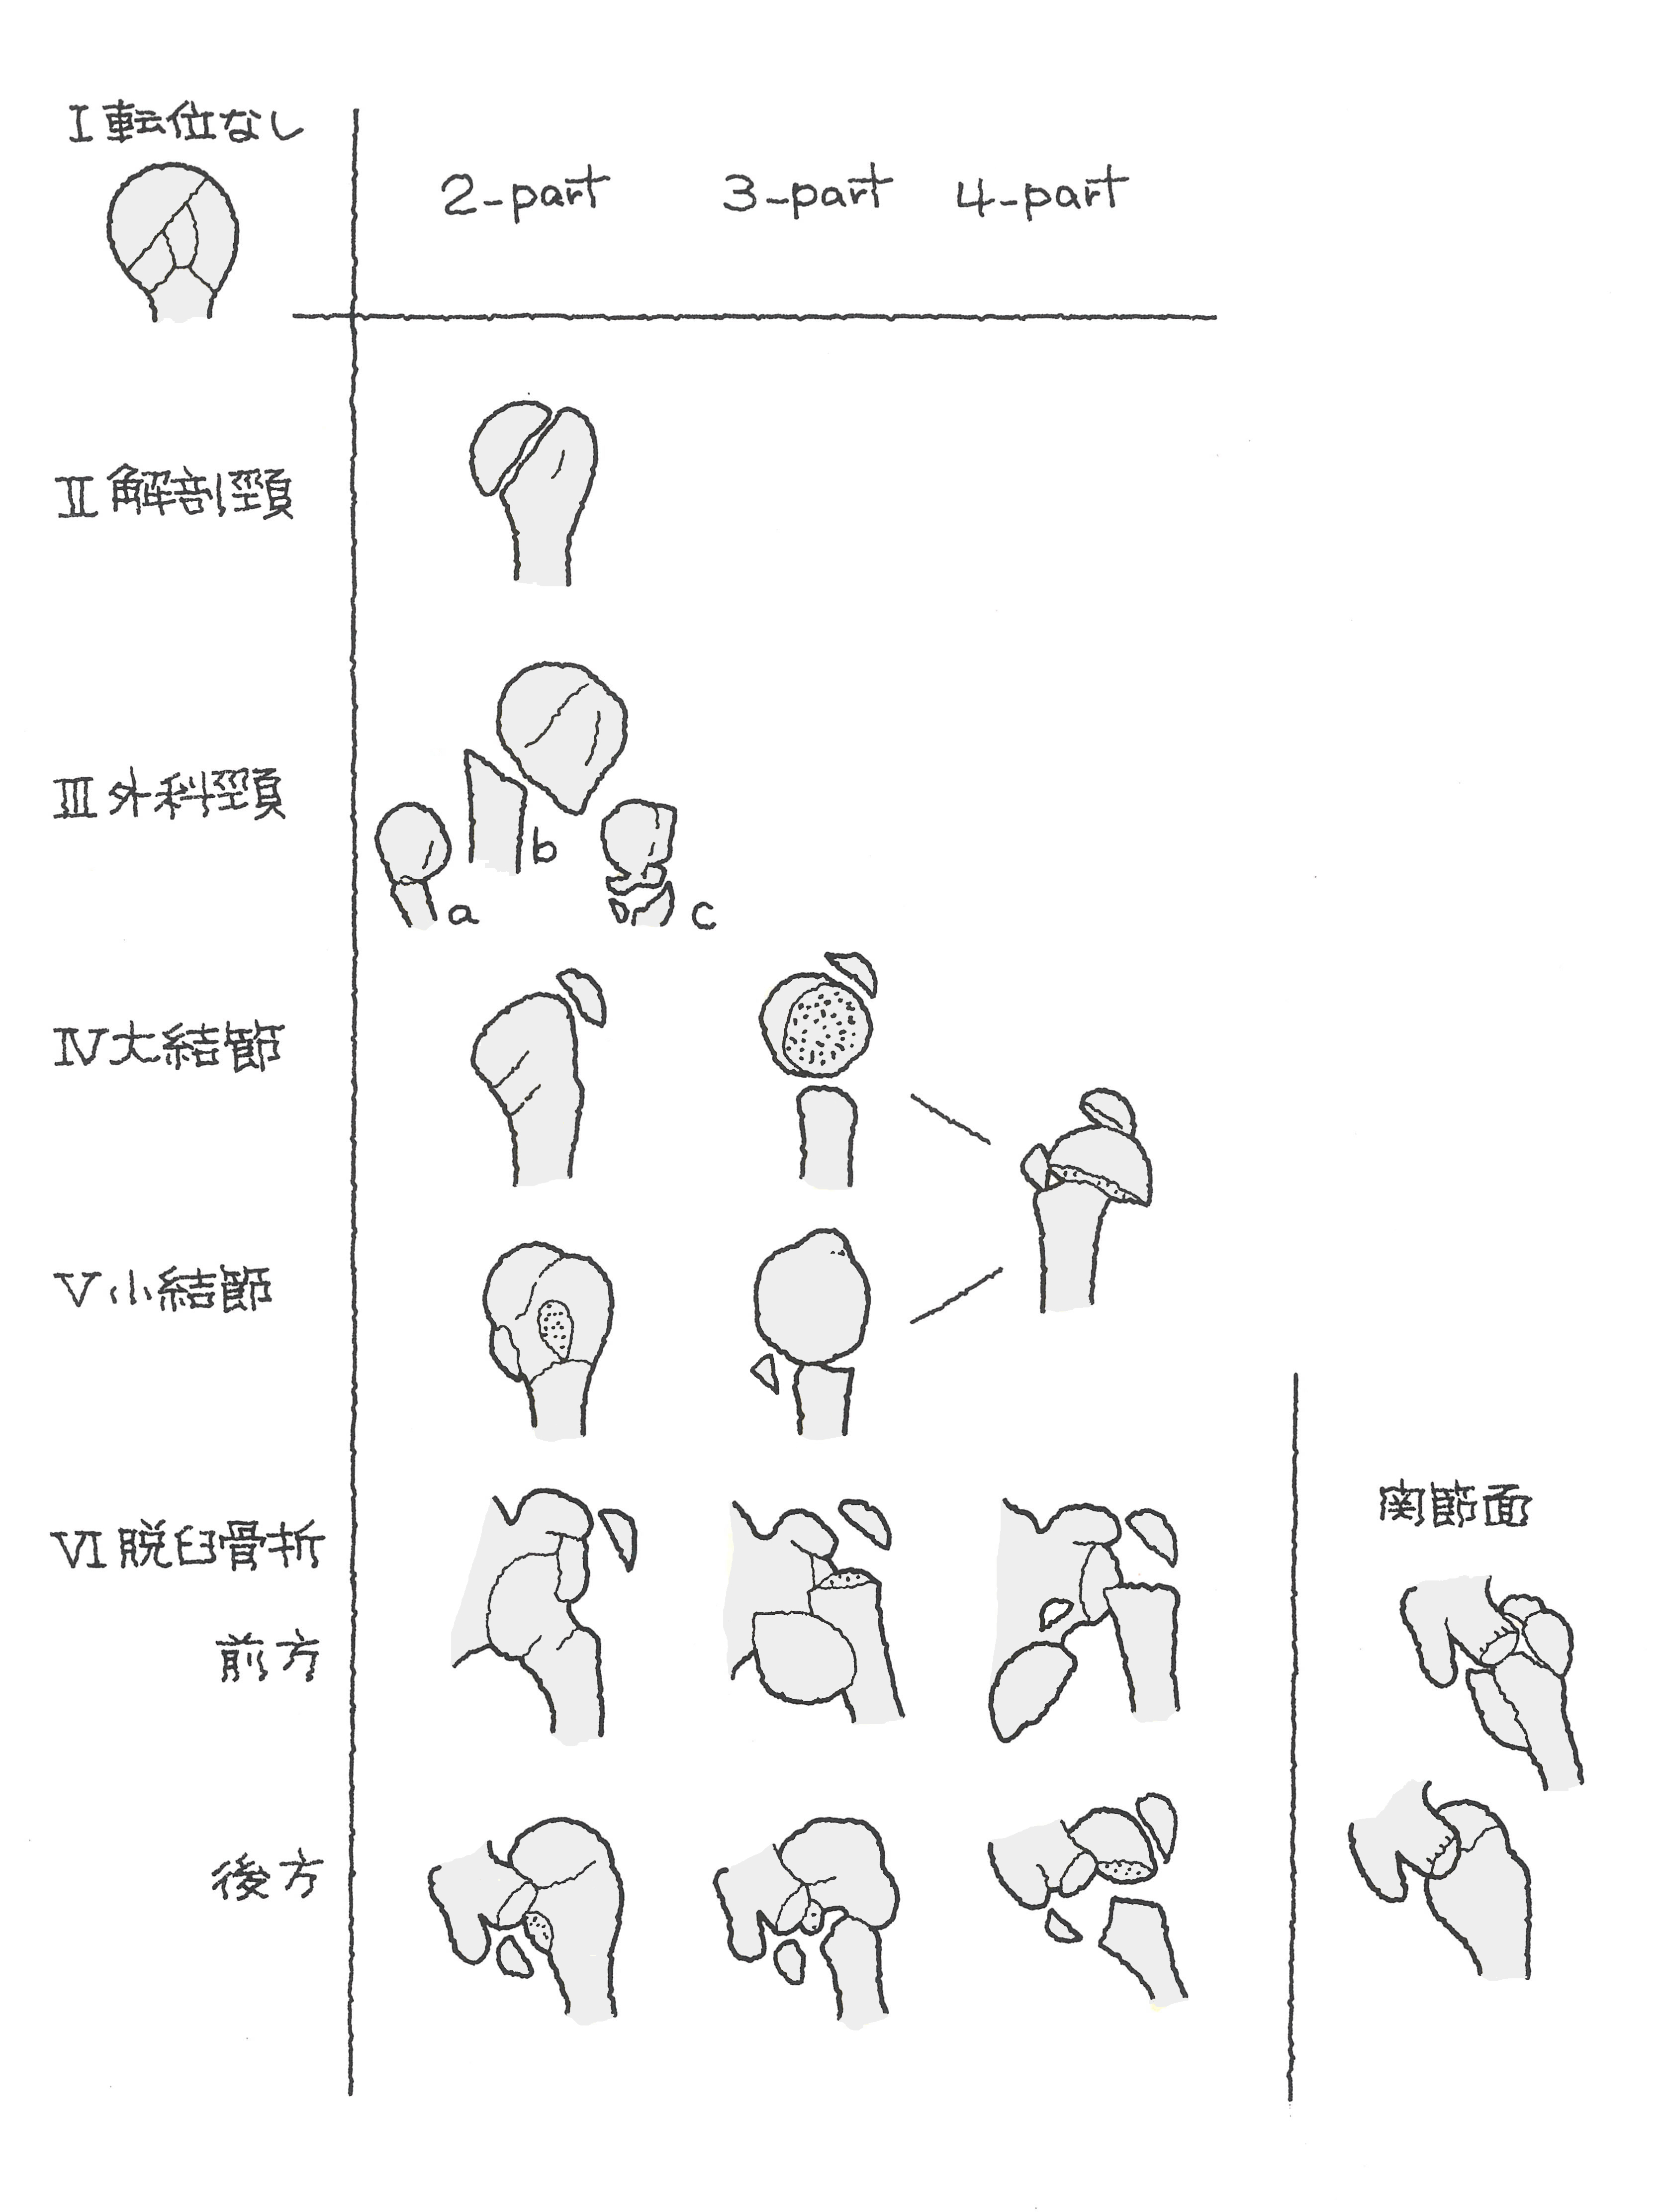

上腕骨近位端骨折におけるneer分類 たくみロドリゲス 運動器理学療法士 Note

上腕骨近位端骨折 一般社団法人 日本骨折治療学会 骨折の解説

上腕骨近位端骨折 一般社団法人 日本骨折治療学会 骨折の解説

上腕骨近位端骨折 じょうわんこつ きんいたん こっせつ 福岡の弁護士による後遺障害 等級認定サポート

上腕骨近位端骨折による後遺障害 後遺症 交通事故弁護士による後遺障害相談